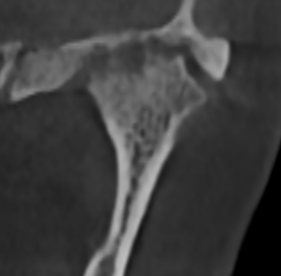

У здорового височно-нижнечелюстного сустава суставные поверхности гладкие и ровные. Такие суставы, как правило, восстанавливаются быстро.

Но, ко мне приходят пациенты с изменёнными суставными поверхностями в виде артроза. Эти суставы повреждены, и в них нарушено нормальное вращение.